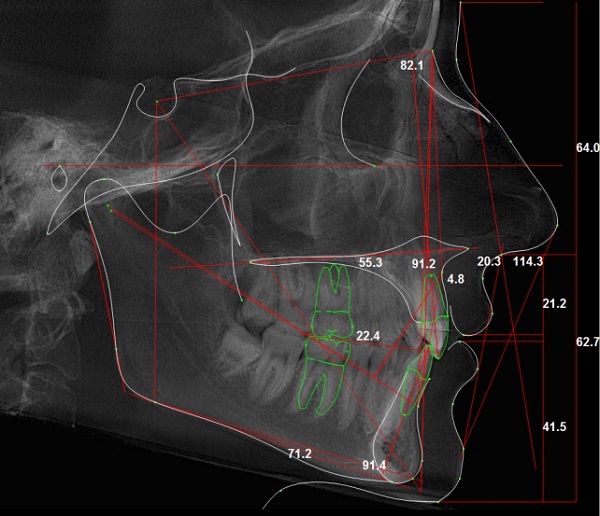

Сплинт-терапия (изготовление специальных кап) позволяет облегчить острые болезненные состояния дисфункции ВНЧС.

На самая главная ОСНОВОПОЛАГАЮЩАЯ ЦЕЛЬ сплинт-терапии: репозиционирование положения нижней челюсти в правильном прикусе. Все отдельные локальные эффекты — это лишь часть комплексной терапии и промежуточные этапы на пути к этой главной цели.